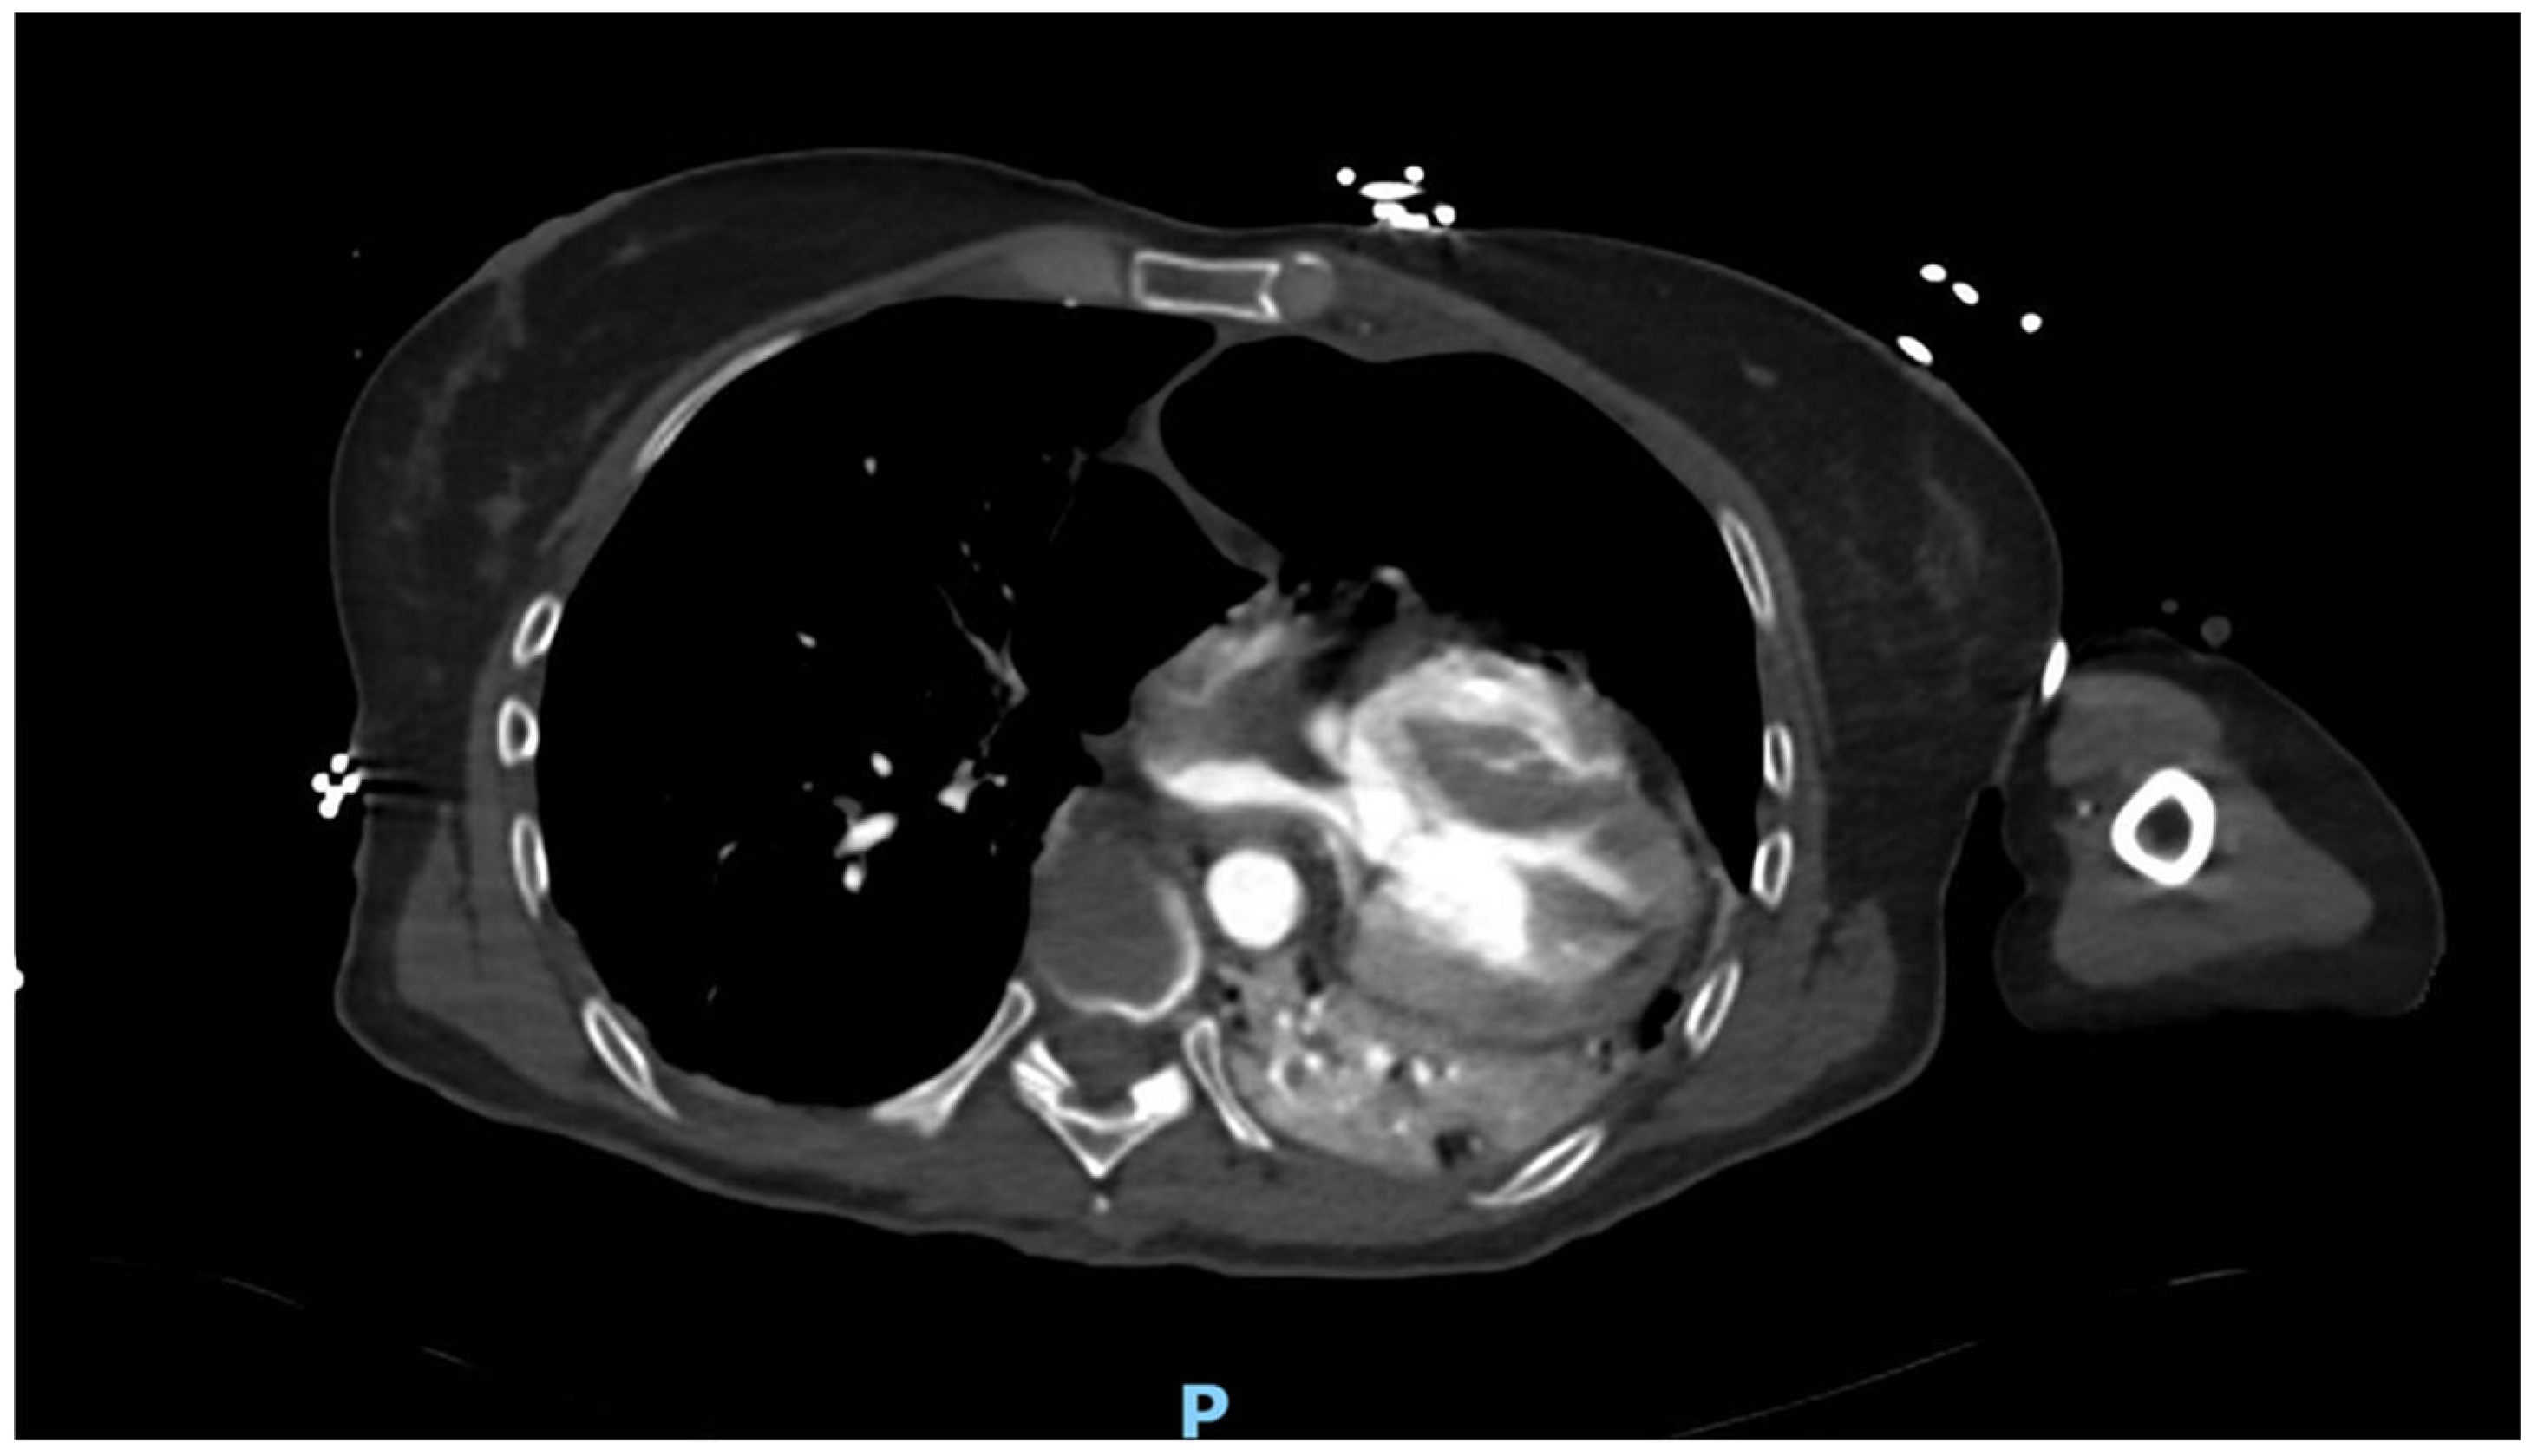

After an expeditious evaluation at the trauma center, a computed tomography (CT) scan revealed that the heart was completely dislocated within the left lung, attributable to a traumatic rupture of the pericardium (Figure 1). Other additional findings included a substantial pneumomediastinum associated with a moderate left pneumothorax, foci of consolidation in the lower lobe, “ground-glass opacities” involving the middle lobe suggestive of parenchymal contusion, no traumatic rupture of the major blood vessels, and no cardiac tamponade.

Figure 1. Computed axial tomography showing heart dislocation. P: posterior side.